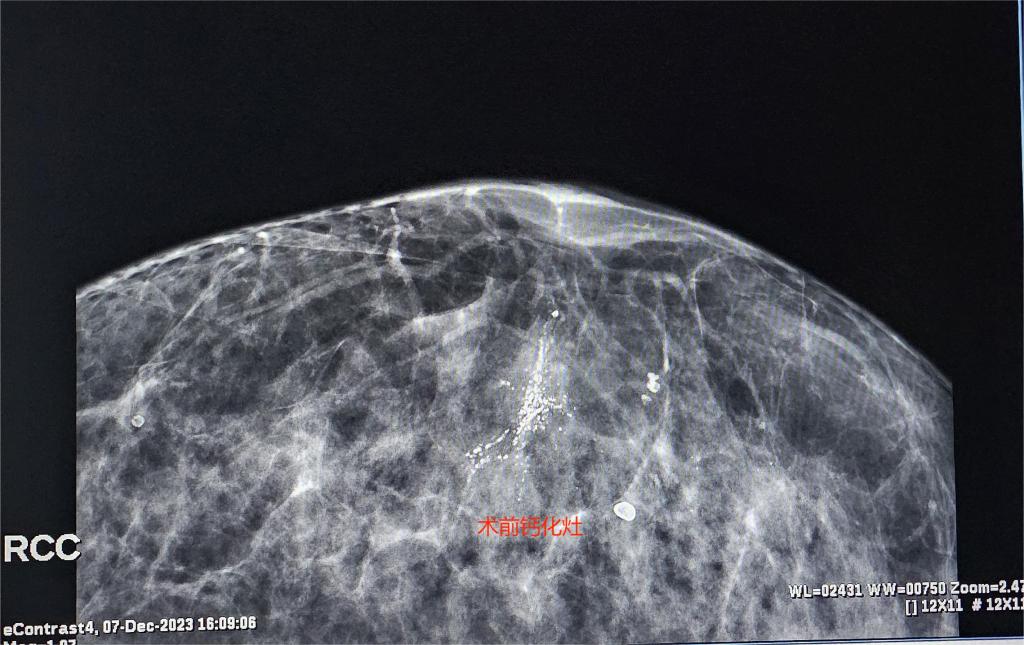

患者女性,57岁,因体检行乳腺X线检查发现“右侧乳腺可疑钙化”,查体后双侧乳腺未触及明显肿块,双侧腋窝未触及肿大淋巴结,复查乳腺X线提示“右乳下象限段样分布细小多形性及粗糙不均质钙化,BI-RADS 4类”,不排除恶性病变。患者入院后科室进行多次术前讨论,决定为患者行Pristina Serena活检机器人三维立体定位下乳腺钙化微创旋切活检术。术中利用X线定位技术,精准找到并成功切除钙化病灶,目前患者恢复良好。

乳腺钙化是乳腺癌常见表现病变之一,及早发现并治疗钙化灶对预防和早期诊断乳腺癌具有重要意义。过去,对于乳腺钙化的治疗主要以开放手术切除为主,但这种方法切除目标不精确、定位困难、创伤范围较大、影响乳房外形、恢复周期长。